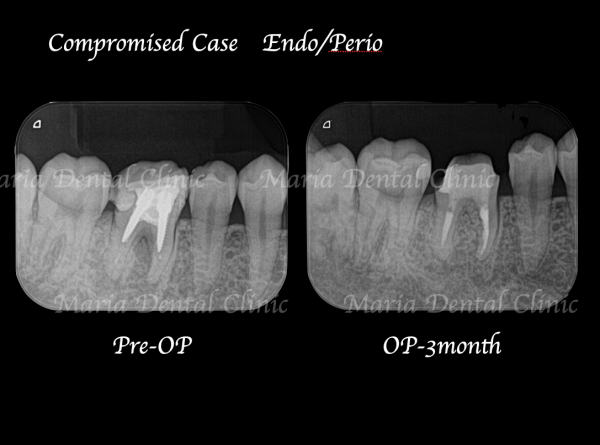

術前の写真を確認すると根の先端から広がる病変の影は歯の股の部分まで大きくなっていることが確認できます(術前写真②)

通法通り根管治療を施したことで歯ぐきの腫脹は改善したものの、分岐部(歯の股の部分)の歯周病に治癒傾向は確認されず(写真1術前)歯周病の治療に移行する判断をしました。

歯周組織再生療法3ヶ月後には分岐部(歯の股の部分)に確認されていた歯周病(術前写真)は完全に治癒していることを確認しました(術後3か月写真)。また同時に、術前に確認できた根尖性歯周炎も綺麗な治癒が確認できたことから最終補綴処置へ移行しました。今後最低2年間は歯肉、根尖周囲組織の治癒経過を患者様にご協力いただき確認していく予定です。